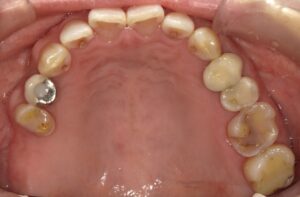

左はインプラントを入れる前に右は入れた後になります。向かって左側の歯が増えて

よく噛めるようになりました。